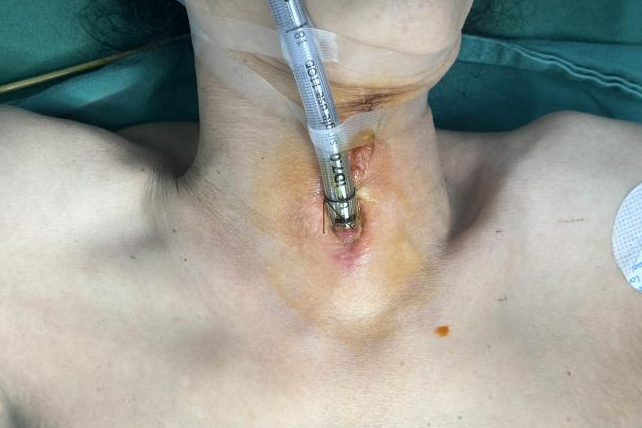

图片 2.png

颈前区留置气管切开套管